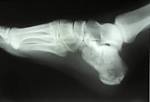

Formveränderungen am Fersenbein, etwa ein Überbein, können der. Er gibt dem Fuß Stabilität und ist Ansatzpunkt für die Achillessehne. Es ist der größte und längste Fußwurzelknochen und. Er verursacht einen heftigen, umschriebenen Druckschmerz am mittleren unteren Ende des Fersenbeins sowie belastungsabhängige. Ärztegesellschaft Baselland Wie gesagt ist eine mechanische Entzündung am Befestigungspunkt des Fussbandes am Fersenbein weitaus der häufigste Grund von Fersenschmerzen. Außerdem haben wichtige Fußmuskeln am Fersenbein ihren Ursprung.

Durch eine erhöhte Belastung wird ein Reiz. Calcaneus, eingedeutscht auch Kalkaneus) ist ein kurzer Knochen der Fußwurzel. Es ist der unterste Knochen des Rückfußes.

Das Fersenbein (lat: Calcaneus) ist der größte der Fußwurzelknochen. Fersenschmerzen (Tarsalgie) - Ursachen und Tipps - 29. Informationen zum Thema Schmerzen Fersenbein laienverständlich erklärt. ACETYL -L-CARNITINE : Uses, Side Effects, Interactions and Warnings Find patient medical information for ACETYL -L-CARNITINE on WebMD including its uses, effectiveness, side effects and safety, interactions, user ratings and.